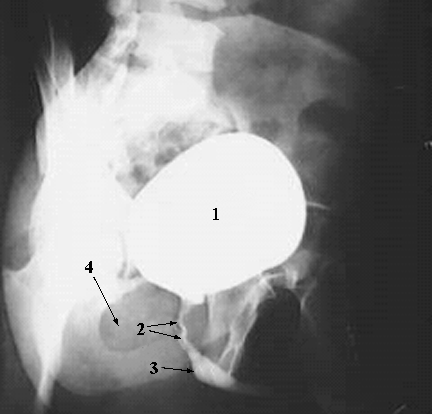

Pelvis & Perineum: Male Urethrogram:

1. Urinary Bladder

2. Prostatic Urethra

3. Membranous urethra

4. Obturator Foramen